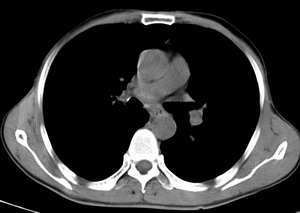

男,58岁,咳嗽1月加重1周,伴痰中带血

左肺上叶胸膜下不规则团块阴影,内见空泡,边缘光整,肺纵比率>50%,支持左肺癌的诊断。

ct:左上肺块状影、其内徐点状气体外蜜度大致均匀。周围粗大索状影

其内透光影仔细观察像是支气管,病灶周围有渗出改变,该病灶不考虑感染性病变,机化性肺炎能排除吗

理由:1 病灶有恶性肿瘤的特征:空泡征,毛刺,棘状突起

左上肺病灶与胸膜脂肪线存在,未见明显胸膜凹陷征,虽然病灶边缘不规则,但未见明显“短毛剌、切迹征、免耳征、血管束集征”,其间亦见条索状、斑点状影,认为左上肺结核或炎性病变>周围型肺癌。

病灶比较虚 周围有明显渗出 卫星灶及条素影 病灶边缘有棘突 胸膜外脂肪层存在考虑结核

考虑肺结核可能性大。理由1.病灶形态不规则,其周有卫星灶,2.病灶没有毛刺征,灶周出现粗大索条影.